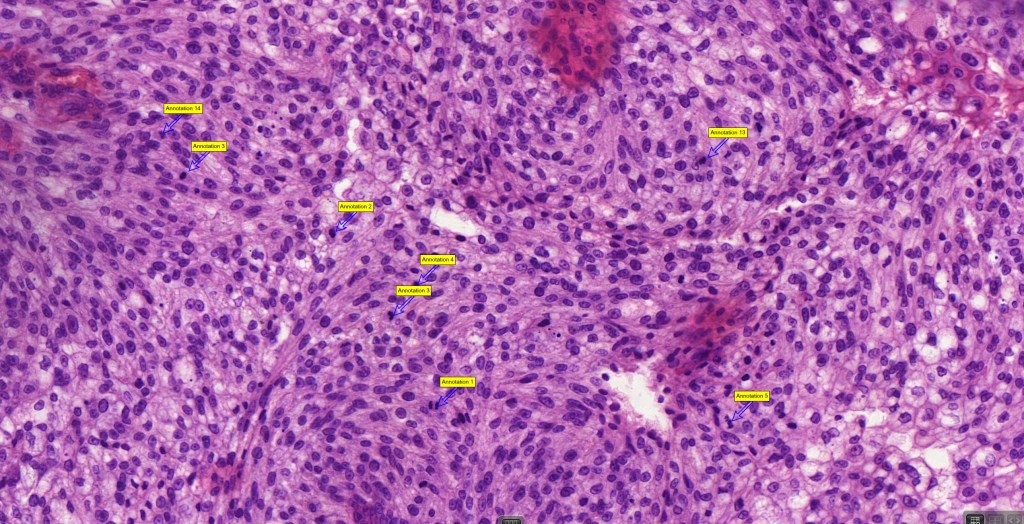

Histological features

•May affect the tumor in part or whole

•Enlarged cells with copious eosinophilic, foamy or clear cytoplasm (some authors include melanoma with clear cell change in the same category)

•Variable pigmentation

•Nuclei vesicular or hyperchromatic

•Pleomorphism is not generally marked and indeed can be very subtle

•Variable mitotic activity